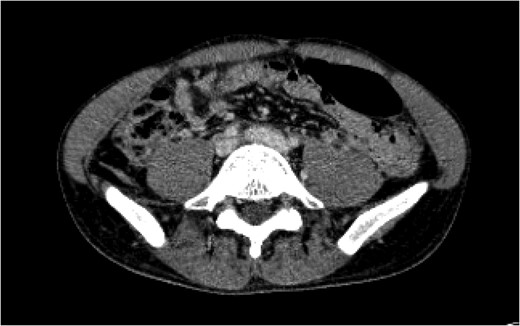

A 24-year-old man was brought by ambulance to our facility after having been involved in an unhelmeted motorcycle collision. He presented with sinus tachycardia up to 123 beats per minute, a Glasgow Coma Score of 15, and had an obvious deformity of the right lower extremity. His tachycardia improved with 2 L of crystalloid fluid bolus. He was stabilized in a cervical collar and a Sager traction splint on his right lower extremity and taken for CT scans of his head, cervical spine, chest, abdomen and pelvis as well as plain films of his extremities. According to our institutional protocol, he underwent CT angiogram of his neck given his skull base fracture. He was found to have a right kidney laceration with active extravasation, two large hepatic lacerations without active extravasation, a right midshaft femur fracture, bilateral distal radius fractures, a left occipital condyle fracture, a dissection of the left internal carotid artery, and pooling of IV contrast near the bifurcation of his inferior vena cava (IVC). This was concerning for a vena cava or iliac vein injury (Fig.

Figure 1:

A CT of the abdomen and pelvis taken on arrival (Day 1) showed a blush of contrast at the bifurcation of the common iliac veins.